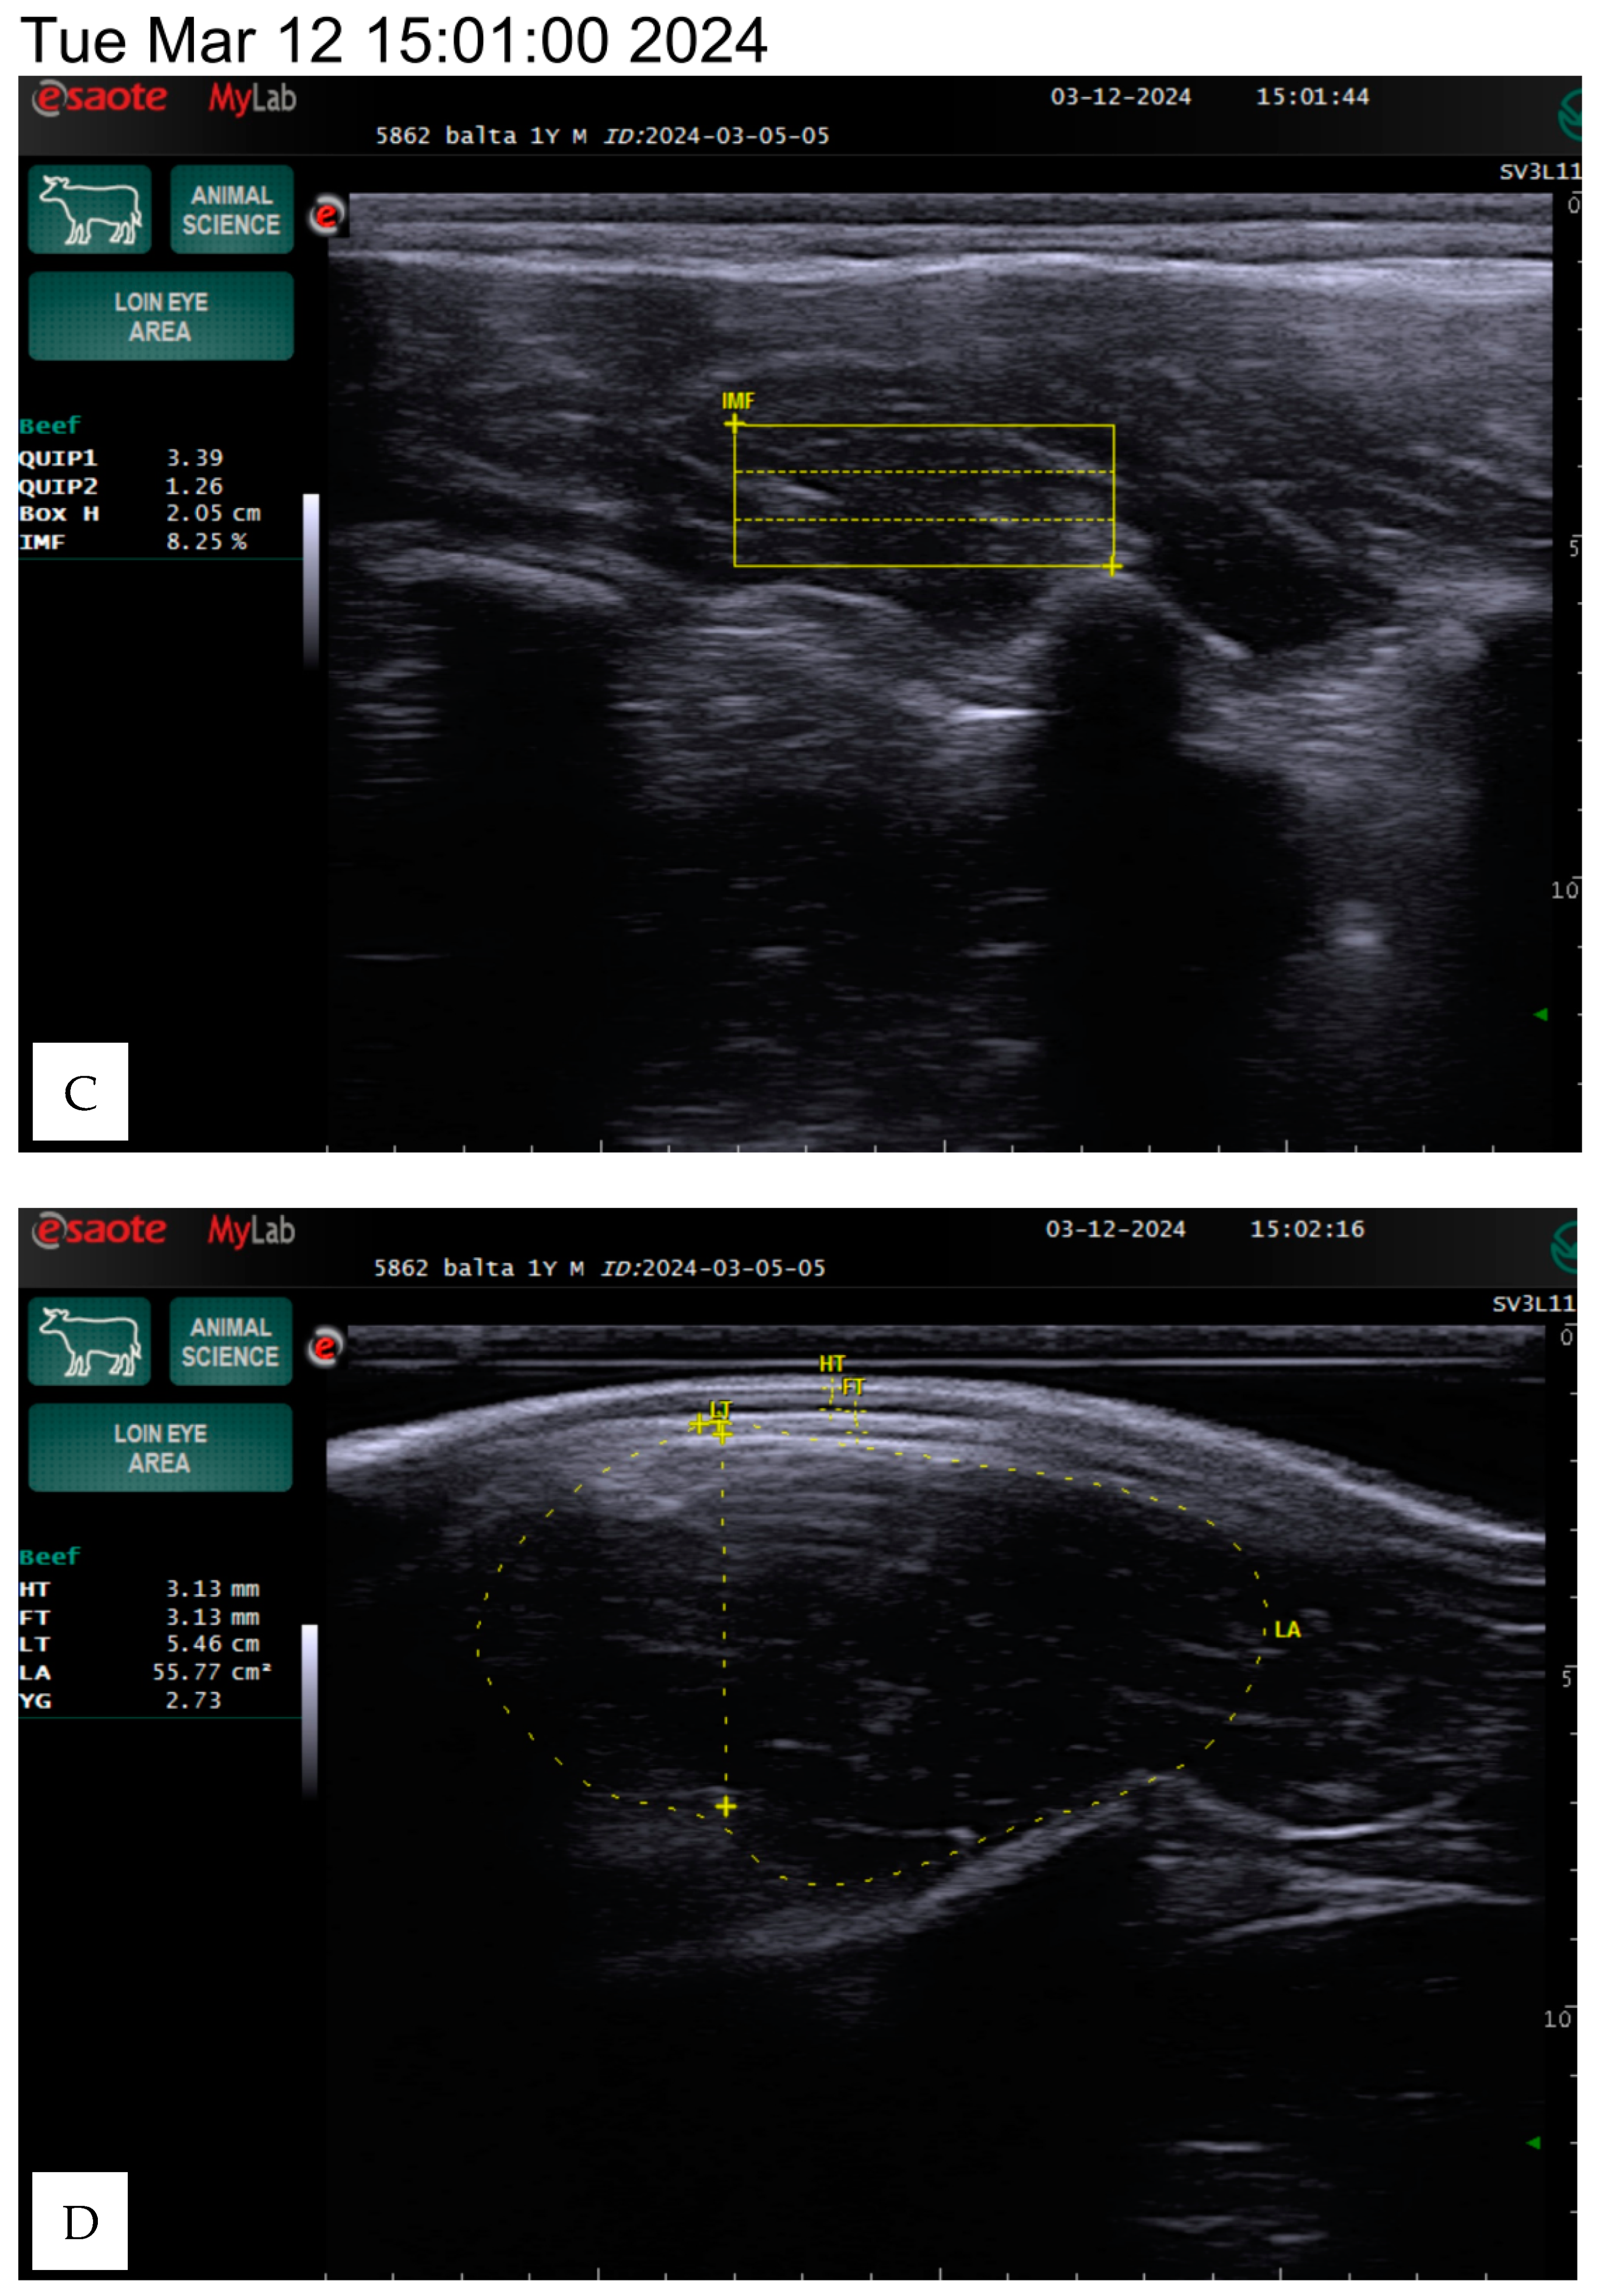

The animals were kept under the same conditions and were fed a total mixed ration based on a weight range of 350–600 kg. The ration primarily consisted of 3.5–6 kg of concentrates (barley, maize, oats, peas, and wheat) and 10–20 kg of grass hay, with a protein content of 226–426 g and a dry matter content of 7.21–13.56 kg. The carcass quality indicators were estimated on live animals using an ultrasound linear transducer using a silicone sleeve for the loin eye area with a frequency range of 4.5 to 6.5 MHz and a depth of 8.8 to 13 cm on the 12th and 13th ribs, following the methodology of Silva et al. [13], as presented in Figure 1.

Figure 1.

The example ultrasound images of the longissimus dorsi muscle of the Angus bulls, weights of 782 kg, IF 3.59% (A,B) and 485 kg, IF 8.19% (B,D). HT—hide thickness, FT—fat thickness (mm), LT—loin thickness (cm), LA—loin area (cm2), YG—yield grade, BH—box height (cm), IF—intramuscular fat (%).

The area of the longissimus dorsi was measured in square centimeters between the 12th and 13th ribs by determining the perimeter of the cross-sectional image displayed on the screen (Figure 1). The longissimus dorsi muscle is a value of the ratio of muscle to lean product of the animal. Backfat thickness is one of the major quantitative traits that affects carcass quality in beef cattle and has been used to predict carcass retail yield components in live animals. The amount of intramuscular fat determines the indicator, known as marbling.

The evaluation parameters included body weight, hide thickness, fat thickness, loin thickness, loin area, yield grade, box height, and intramuscular fat percentage, which we determined using the Measure mode in the ultrasound program. The box height depends on the screen image and the size of the intercostal area, so the data may vary between animals, as shown in Figure 1.